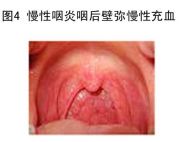

| 2021年7月26日 (一) 20:01 | 慢性咽炎.jpg (文件) |  |

39 KB | 77921020 | Uploaded with SimpleBatchUpload | 3 |

| 2021年7月26日 (一) 20:01 | 慢性咽喉炎.jpg (文件) |  |

34 KB | 77921020 | Uploaded with SimpleBatchUpload | 3 |